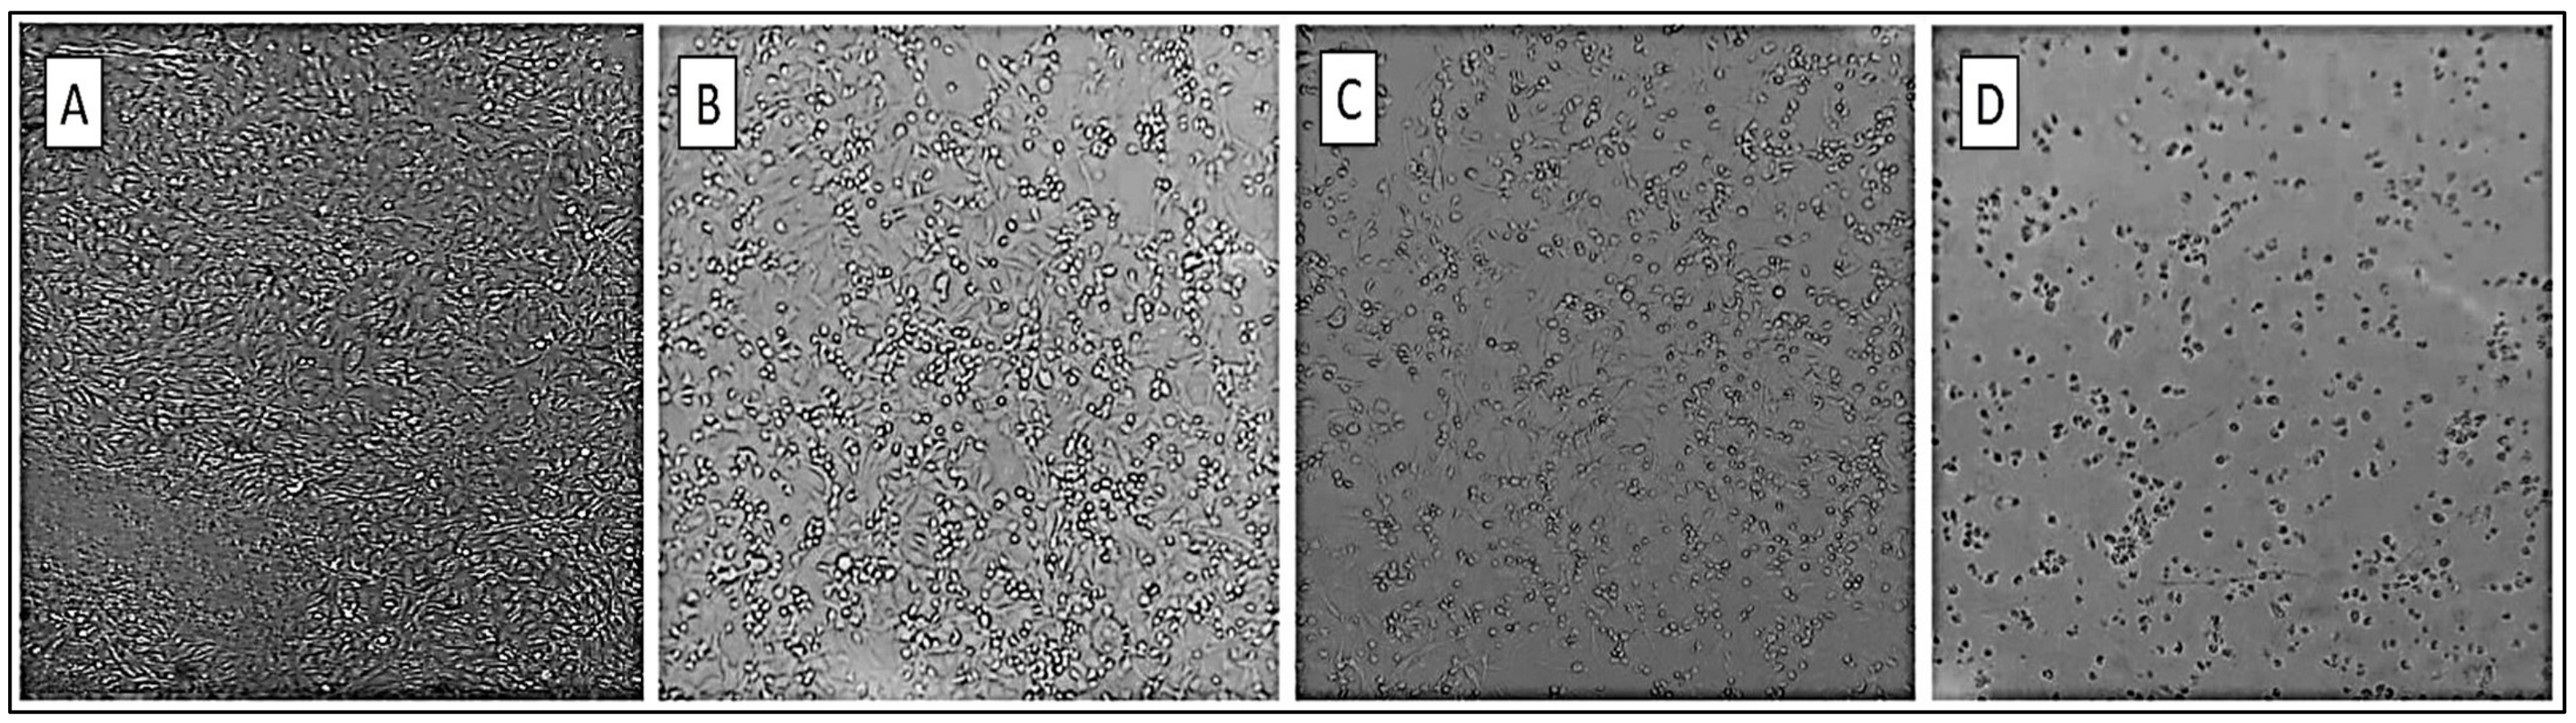

3.1. Cell Culture